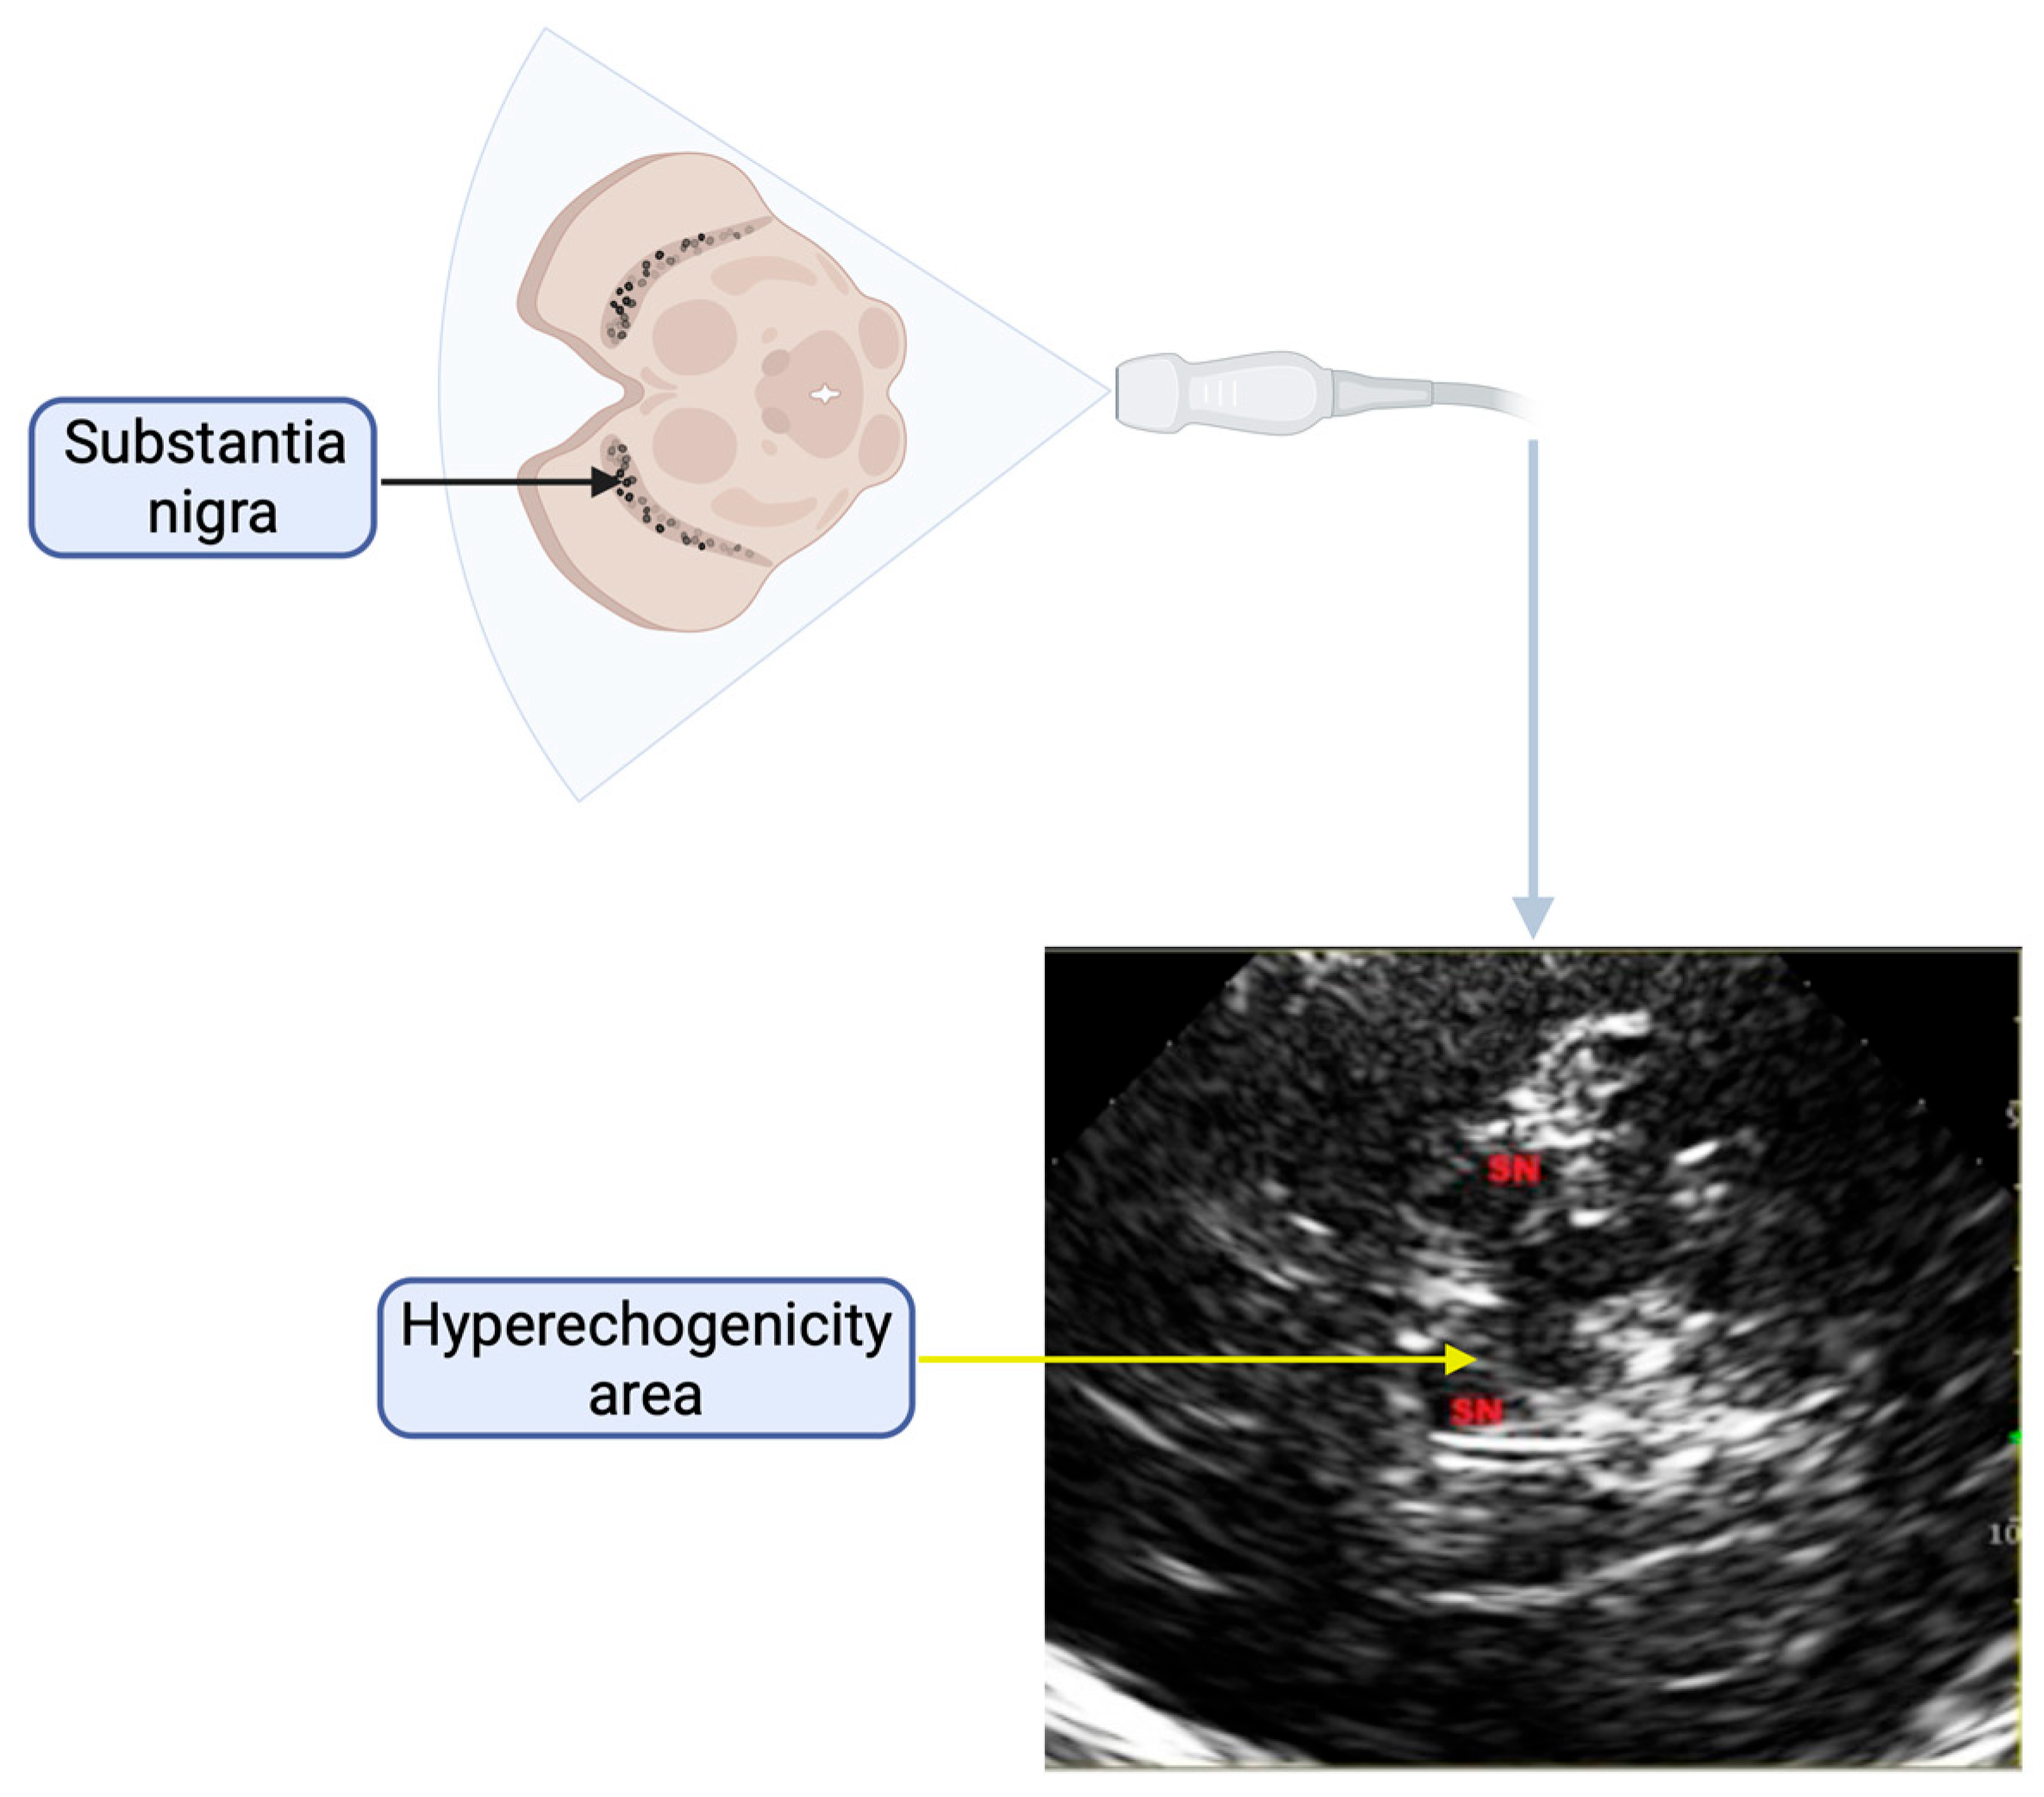

| SN | Substantia nigra |

| TCS | Transcranial ultrasonography |

- Zhang, Y.Y.; Jiang, X.H.; Zhu, P.P.; Zhuo, W.Y.; Liu, L.B. Advancements in understanding substantia nigra hyperechogenicity via transcranial sonography in Parkinson’s disease and its clinical implications. Front. Neurol. 2024, 15, 1407860. [Google Scholar] [CrossRef]